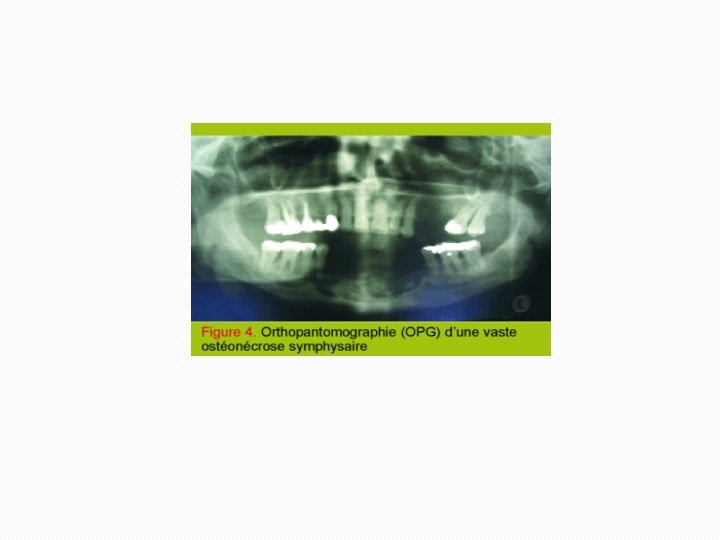

Desmodontite chronique sur la 37, se compliquant d’une cellulite génienne Deux mois après extraction de la 37, persistance de la suppuration et importante atteinte osseuse à la radio